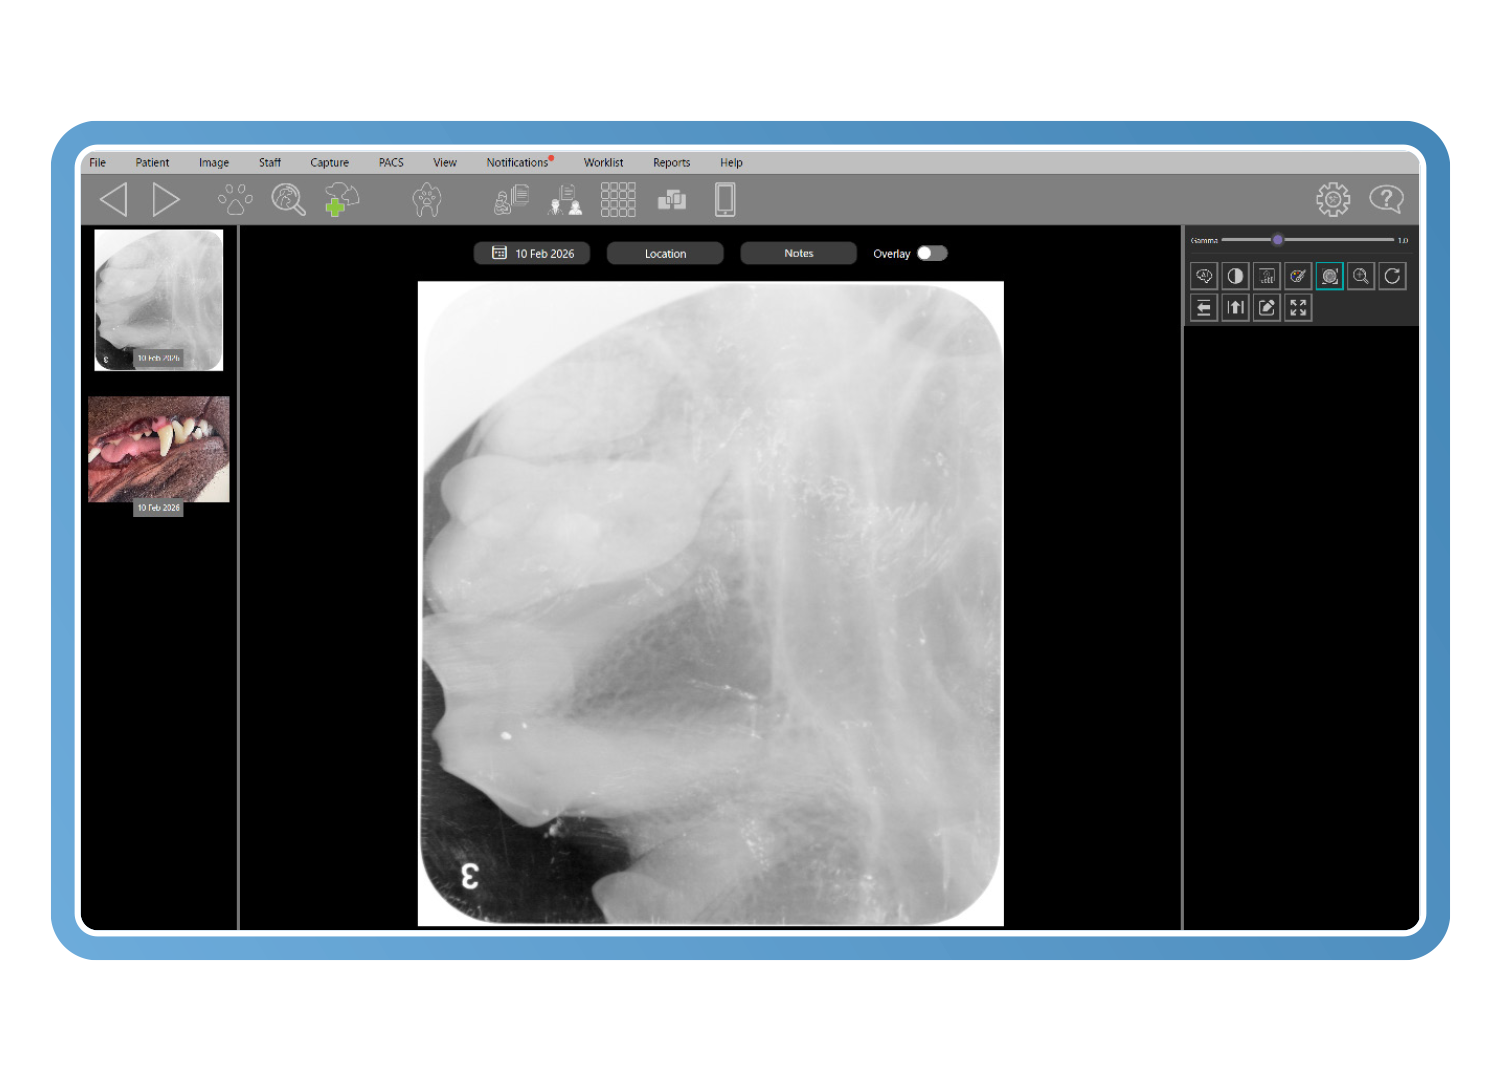

Herramientas diagnósticas específicas para veterinaria

Las herramientas avanzadas de imagen veterinaria mejoran el detalle diagnóstico incluso a partir de imágenes subóptimas. El análisis de Clarity detecta cambios con una diferencia de contraste de tan solo un 2 %, mientras que los filtros inteligentes y la visualización en pseudocolor revelan la pérdida ósea y los detalles periodontales, reduciendo las repeticiones y convirtiendo imágenes de baja calidad en imágenes diagnósticas.

Diseños intuitivos de boca completa y formato libre

Cree conjuntos de imágenes diagnósticas claros y completos utilizando diseños intuitivos de boca completa y formato libre para múltiples especies. Las imágenes se colocan automáticamente en la posición correcta, con una edición sencilla mediante arrastrar y soltar. Combine radiografías y fotografías para presentar una historia diagnóstica coherente y fácil de entender.